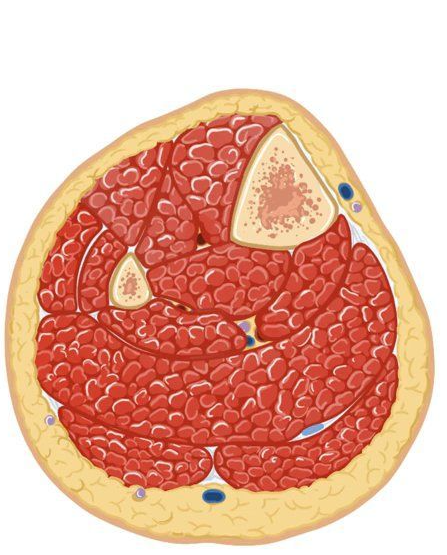

ACUTE COMPARTMENT SYNDROME

fractures (most common)

other: hemorrhage, crush injuries, vascular puncture, severe circumferential burns / IV drugs / revascularization procedures / poor-fitting casts / ortopaedic intervention combined with patient taking anticoagulants

* Clinical Features

legs + forearm (most common)

early signs: severe deep pain (unless pt had anaesthetic nerve block/epidural)/ swelling / tense muscle compartment / parasthesias

late signs: ↓pulse / anesthesia / function loss / paralysis

measurement of intracompartmental pressure ( >20mmHg =abnormal / >40mmHg = diagnostic)

fasciotomy

inexperienced clinician = inadequate decompression → myoglobinuria → renal failure (needs aggresive IV fluids)

death of muscle groups (withing 4-6h)